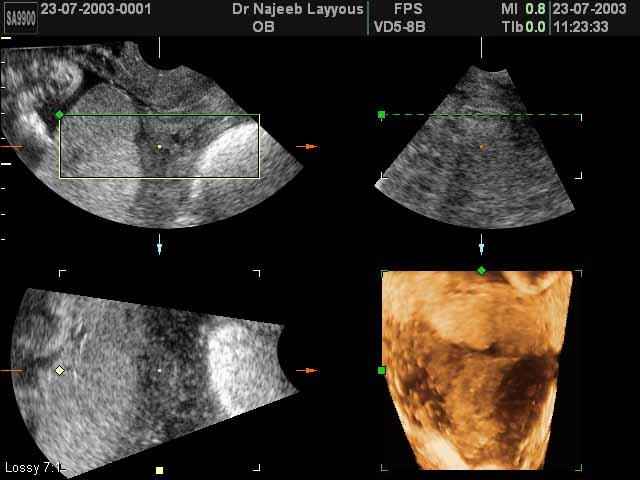

- لقطات فيديو للجنين بجهاز الموجات فوق صوتية رباعي الأبعاد

- صور لوجه الجنين في داخل الرحم

- صور جانبية لرأس الجنين